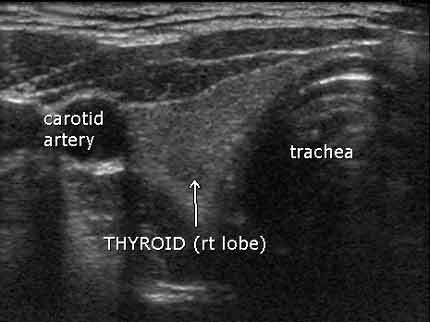

Ultrasonido del lóbulo derecho de la tiroides, proyección hacia arriba desde la barbilla hacia la parte superior de la cabeza

Nota: Las imágenes se muestra para fines ilustrativos. No trate de sacar conclusiones comparando esta imagen con otras en el sitio. Solamente los radiólogos calificados deben interpretar las imágenes.